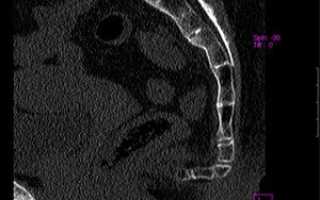

Признаки перелома копчика. Разбор снимка нейрохирургом с 25-летним опытомПризнаки перелома копчика. Разбор снимка нейрохирургом с 25-летним опытом

2. Рентгенография копчика. Исследование выполняется в прямой (лежа на спине с прямыми ногами) и боковой (на боку с согнутыми ногами) проекциях. Перелом не всегда виден на рентгеновском снимке, так как мелкие кости копчика могут быть скрыты мягкими тканями.

3. Компьютерная томография позвоночника. Это наиболее информативный метод, позволяющий получить детализированное изображение плотных структур.

Рентгенография